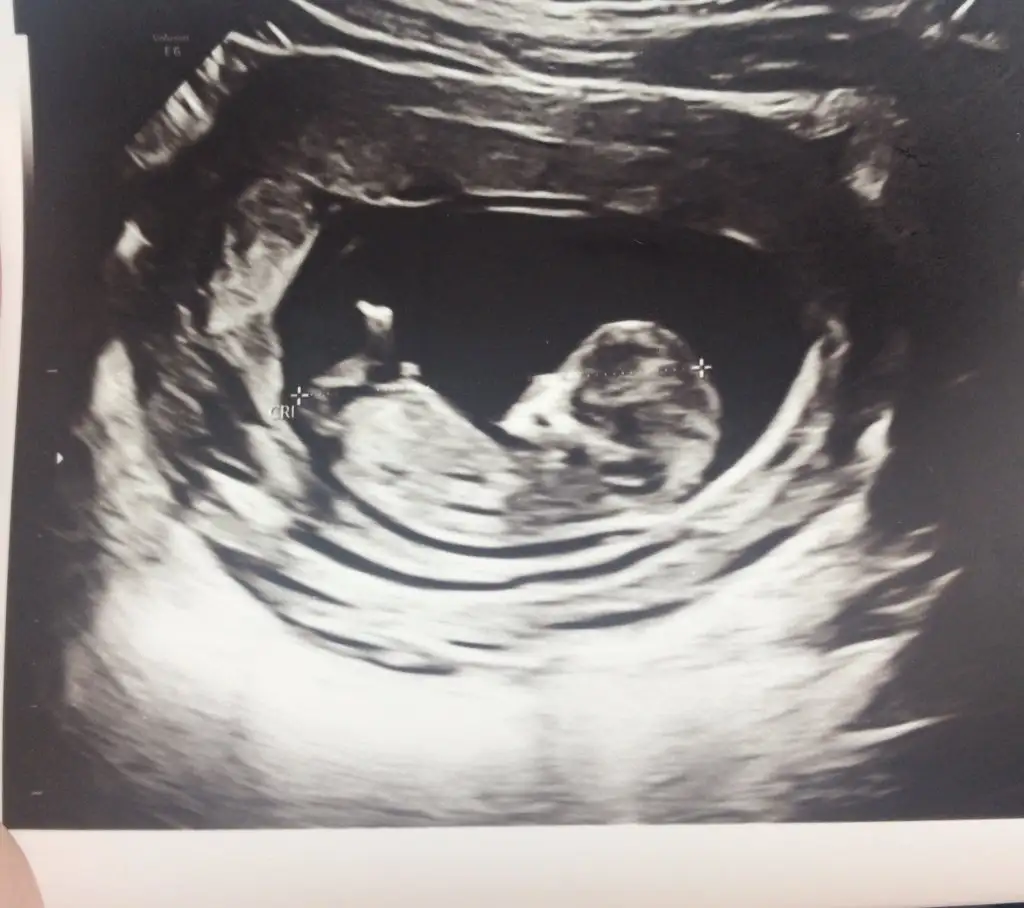

5 ve 14. haftaya kadar olan ultrason fotolarınızı paylaşın. Vajinadan mı yoksa karından mı çekildiğini ve kaç haftalık olduğunu da mutlaka belirtin.:anneadayı:

Merhaba canım lütfen lütfen benimkini de yorumlar misinin karın ultrasonu